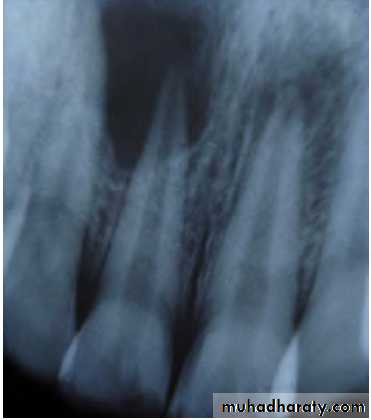

• Clinically:“Pink Tooth” appearance• Radiographic changes:

– Radiolucent enlargement of pulp canal

– Original root canal outline distorted

– Bone changes are seen only when root perforation into periodontal ligament takes place.